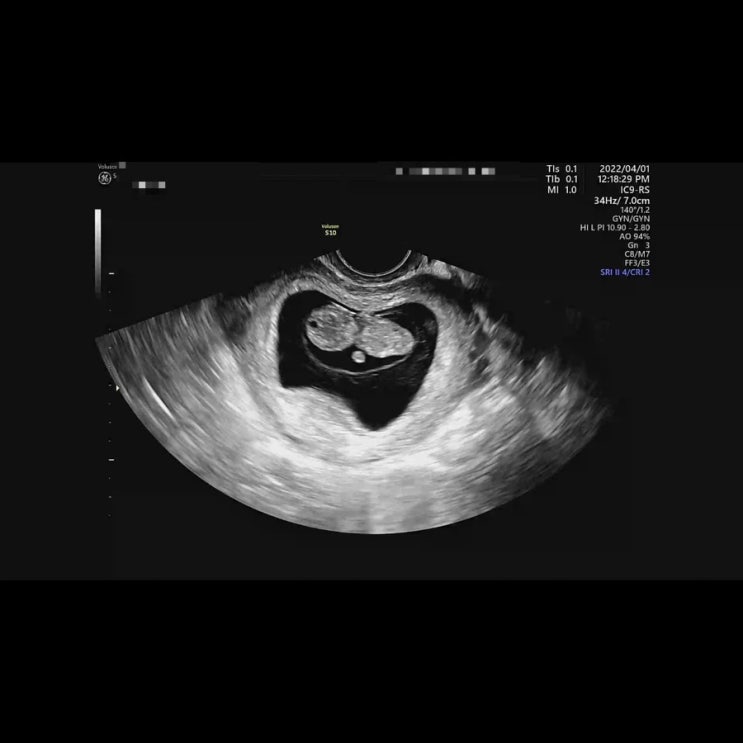

[임신기록] 칙촉이와의 21주차 기록하기 / 임신21주

친정에서 정신없이 지나간 21주의 기록 시작 남편 부산 출장으로 21주자 0일부터 친정에서 시작했다 ˃̵͈...

[임신기록] 임신 20주까지의 기록 몰아쓰기

결혼식 전 알게 된 소식으로.. 무척이나 혼란스러웠지만 우리 인생에 칙촉이 등장! 늦었지만 임신 20주까지...